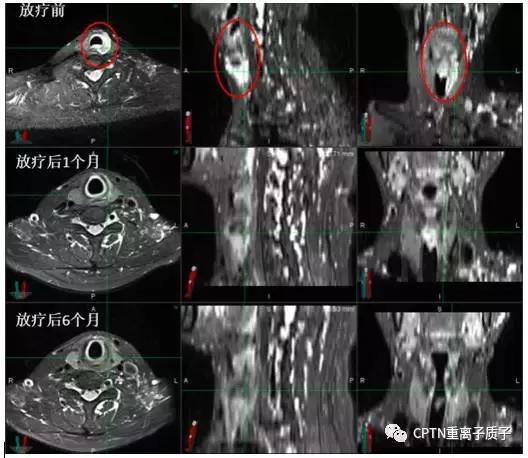

例:

图为高危局限期前列腺癌患者,初诊 PSA最高达21.359ng/ml。既往有高血压、冠心病等内科基础疾病,手术风险大,后行根治性重离子治疗联合内分泌治 疗。治疗结束后复查PSA:0.221ng/ml,复查MRI提示前列腺肿瘤从治疗前2.1*1.9cm缩小到0.8*0.8cm(如图所示,红色圆圈部分)。治疗后半年随访PSA:<0.003ng/ml,治疗及随访过程中未出现尿*禁失**、排尿困难等并发症,可以正常参加各类社会活动。